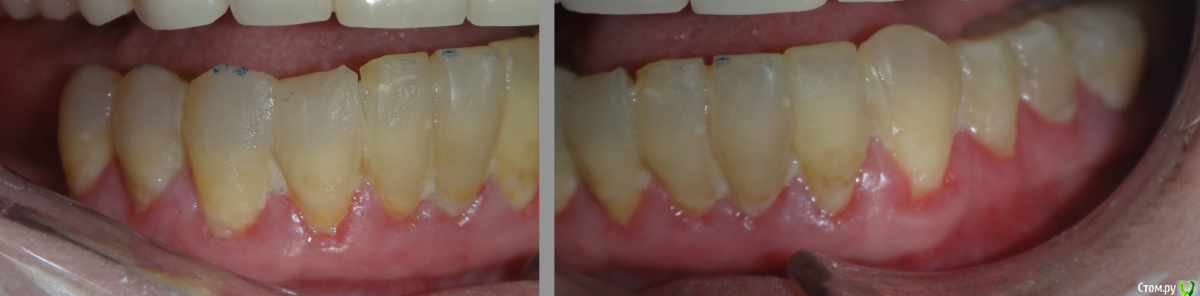

Карен Аванесов Опубликовано 20 ноября, 2015 Поделиться Опубликовано 20 ноября, 2015 На фото фрагмент предстоящего так называемого "тотала", вот конкретно здесь, некоторая загвоздка, зубы надо восстановить (с первого взгляда сразу понятно как), но я хочу уйти от депульпирования и штифтования, вкратце, оставить зубы "живьем" и сделать все адгезивно. Выслушаю Ваше мнение коллеги по поводу конкретно этого сегмента. Ссылка на комментарий

ходок Опубликовано 21 ноября, 2015 Поделиться Опубликовано 21 ноября, 2015 В общем-то здесь изначально не прсматривается показаний к депульпированию - с таким заместительным дентином. Я одной похожей пациентке даже без анестезии работал. Адгезивно возможно - достаточно склерозированный верхний слой убрать. Ссылка на комментарий

carloss Опубликовано 17 декабря, 2015 Поделиться Опубликовано 17 декабря, 2015 Многовато убрали, как по мне 1 Ссылка на комментарий